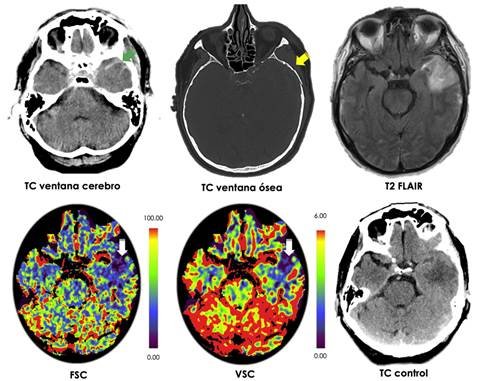

Perfusión Cerebral mediante TC

Mapeo de flujo sanguíneo cerebral para detección de infarto agudo, evaluación de tumor y demencia con rápida adquisición.

Protocolo STROKE (ACV agudo)

Evaluación integral con RM multimodal: perfusión, difusión, tensor e imágenes de susceptibilidad para ACV isquémico y hemorrágico.

CT perfusión cerebral en tiempo real

Protocolos rápidos de perfusión y CTA para evaluación urgente en accidente cerebrovascular, con análisis de mapa de penumbra.

Syngo: post-procesamiento neuro avanzado

Herramientas para mapa de perfusión, análisis espectroscópico y reconstrucciones vasculares con reportes clínicamente accionables.